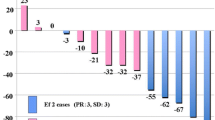

The change of 18F-FDG uptake between baseline and post-treatment scan was -46.82% ± 8.10% (SE) in responders, indicating a reduction of tracer uptake, whereas non-responders showed an increase of 18F-FDG uptake with a ΔSUVmax of 20.40% ± 15.75% (SE). The normally distributed values of ΔSUVmax were significantly different in responders and non-responders (p = 0.0003, unpaired t-test) and were significantly correlated with morphovolumetric response (Spearman’s rank correlation, r = 0.64, p = 0.001). Fig. 1 shows the distribution of ΔSUVmax values in responders and non-responders.

Distribution of ΔSUVmax values in patients allocated in the class of responders and non-responders by RECIST criteria. Responders showed ΔSUVmax values significantly lower than those of non-responders (p = 0.0003, unpaired t-test) and a significant correlation was found between ΔSUVmax values and morphovolumetric response (Spearman’s rank correlation, r = 0.64, p = 0.001). Horizontal bar indicates mean